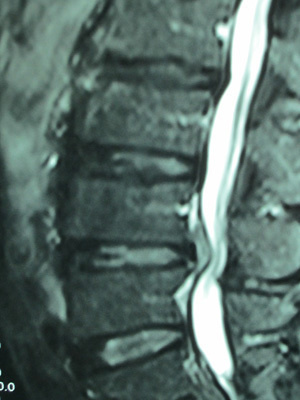

• 椎間板ヘルニア

腰は5個の椎骨からなりますが椎骨と椎骨の間にクッションの役割を果たす[椎間板]があります。

その椎間板は線維輪と髄核で構成されていますが、その髄核が線維輪を破って飛び出した状態が椎間板ヘルニアです。

その症状は腰痛と下肢痛です。

両方の症状をおこすことも多いのですが、腰痛または下肢痛のみという場合もあります。